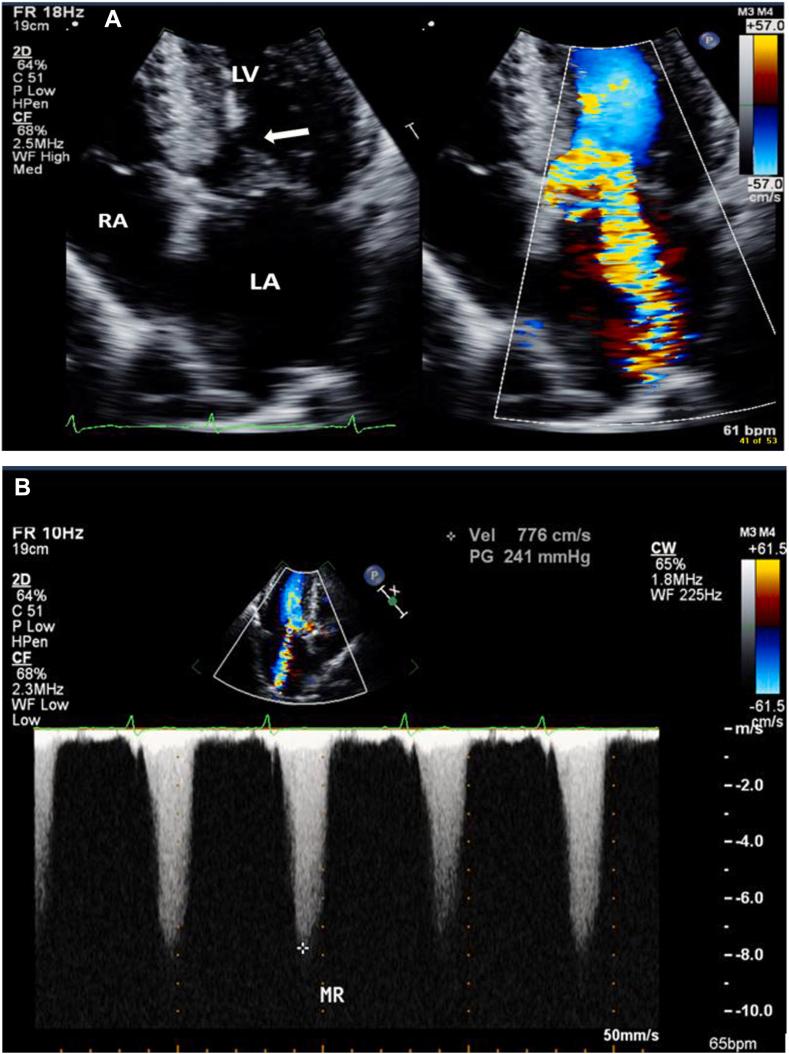

Aortic Stenosis With Dynamic Left Ventricular Outflow Obstruction: Diagnostic and Management Challenges-A Case Series.

• Serial stenoses with AS and HCM can pose diagnostic challenges with echocardiography. • Doppler assessment of AS in this situation can overestimate gradients and severity. • Consider TEE and invasive hemodynamics when diagnostic uncertainty remains.

• 伴有主动脉瓣狭窄(AS)和肥厚型心肌病(HCM)的串联狭窄会给超声心动图诊断带来挑战。

• 在这种情况下,对AS进行多普勒评估可能会高估压力阶差和严重程度。

• 当仍存在诊断不确定性时,考虑经食管超声心动图(TEE)和有创血流动力学检查。